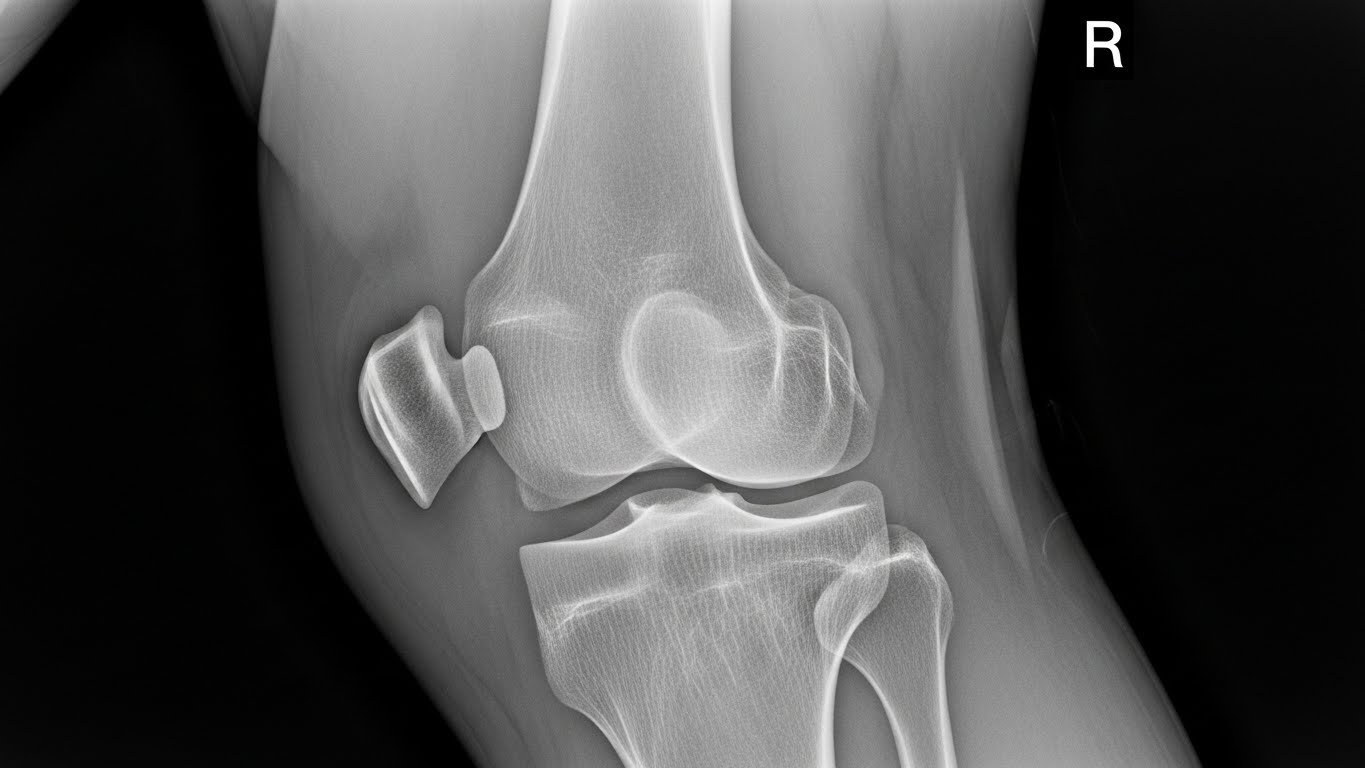

Knees and Long Bones

In growing kids, bony bumps called osteochondromas may develop near joints. They’re often harmless but can hurt if they press on muscles or nerves.

- X-rays – The most common way to see the size and shape of the bone growth.

In nearly all cases, exostosis shows up clearly on an X-ray, helping doctors decide what to do next. It’s important to diagnose exostosis early—especially in children—so treatment can begin if needed.